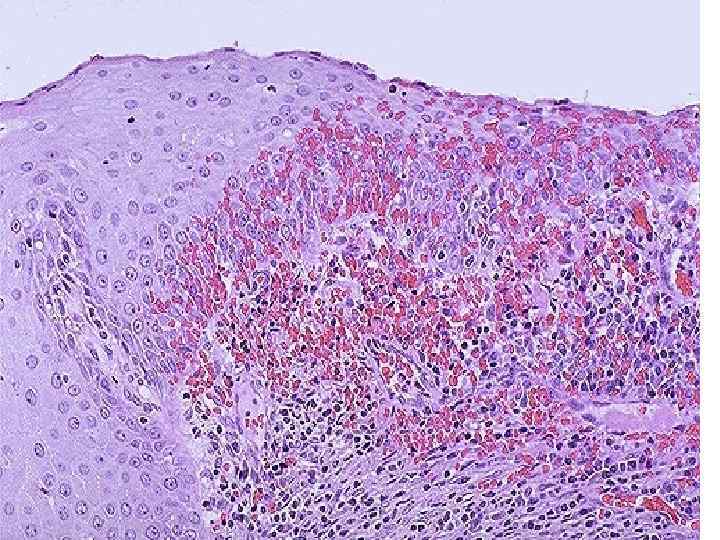

Дисгормональные заболевания шейки матки Эндоцервикоз (железистая псевдоэрозия) n Лейкоплакия n Эритроплакия n n Предраковое изменение дисплазия эпителия

Лейкоплакия слизистой оболочки шейки матки

Рак шейки матки n Рост – экзофитный Гистологически – плоскоклеточный рак n